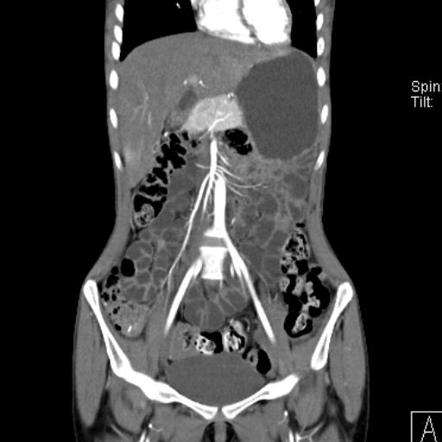

КТ-ентерографія — це спеціалізований вид комп’ютерної томографії, який фокусується на тонкому кишечнику. Перед дослідженням пацієнт випиває контрастну рідину, що розширює просвіт кишки. Також вводиться внутрішньовенний контраст для кращої візуалізації судин та тканин. Це дозволяє отримати чіткі зображення стінок кишечника, оцінити їх структуру, товщину, кровопостачання та виявити патологічні зміни.

Як використовується КТ-ентерографія у діагностиці хвороби Крона? Хвороба Крона — це хронічне запальне захворювання кишечника, яке може вражати будь-яку його ділянку. КТ-ентерографія є одним із ключових методів діагностики та моніторингу цього стану.

- Потовщення стінок кишки. Це одна з найбільш ранніх та характерних ознак запалення. У нормі стінка кишечника тонка і рівномірна, але при хворобі Крона вона стає потовщеною через набряк та інфільтрацію запальними клітинами.

- Симптом «мішені». Так званий «target sign» або симптом «мішені» виникає через шарувату структуру ураженої стінки кишки. На КТ це виглядає як чергування ділянок різної щільності, що відображає набряк слизової та підслизового шару разом із посиленим контрастуванням.

- Активна фаза запалення. У період загострення КТ-ентерографія демонструє інтенсивне накопичення контрасту в стінці кишки, набряк навколишніх тканин та розширення судин брижі (так званий «comb sign»). Ці ознаки допомагають лікарю відрізнити активний процес від хронічних змін і правильно підібрати лікування.

- Звуження просвіту. Тривалий запальний процес може призводити до формування стриктур — ділянок звуження кишки. Це небезпечне ускладнення, яке може викликати часткову або повну кишкову непрохідність. КТ-ентерографія дозволяє оцінити ступінь звуження, його протяжність та вплив на проходження вмісту кишечника.

Окрім запальних захворювань, КТ-ентерографія ефективно використовується для виявлення новоутворень тонкого кишечника, які часто довго не проявляються симптомами.

Метод дозволяє виявити пухлинні утворення навіть невеликого розміру та оцінити їх локалізацію та межі. Лікар може визначити ступінь ураження стінки кишки, виявити ускладнення (кровотечі, обструкцію) та запідозрити метастатичне поширення.